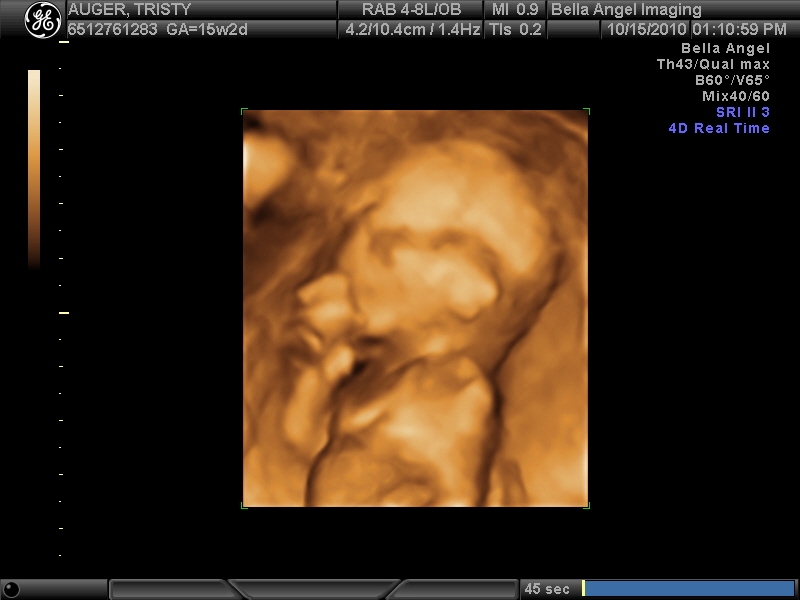

AND WE ARE......TEAM BLUE!!!!